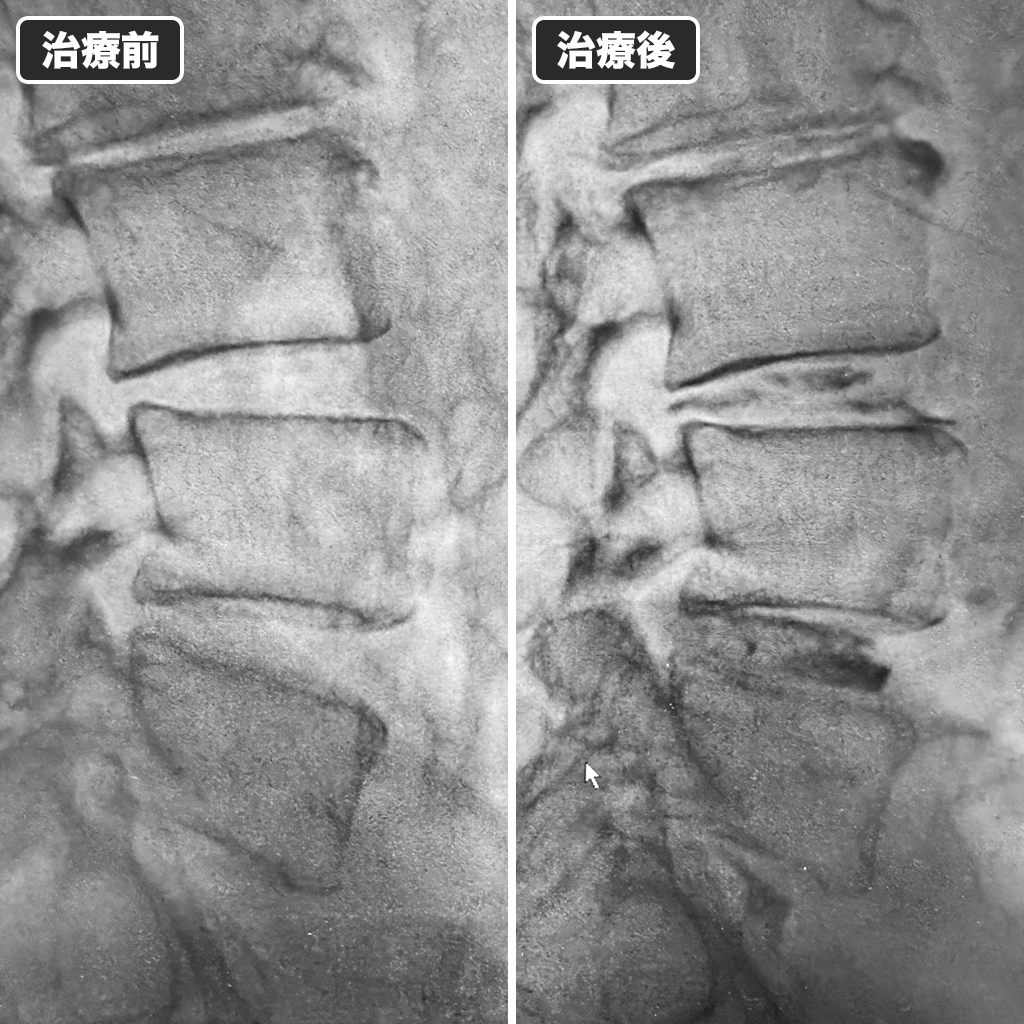

治療前後のレントゲン写真

治療前後のレントゲン写真です。左側が治療前、右側が治療後になっています。2ヵ月前に坐骨神経痛が出現したばかりですから、神経障害が後遺症になっている可能性は低いとご説明しました。十分な改善が期待されることをお伝えしました。